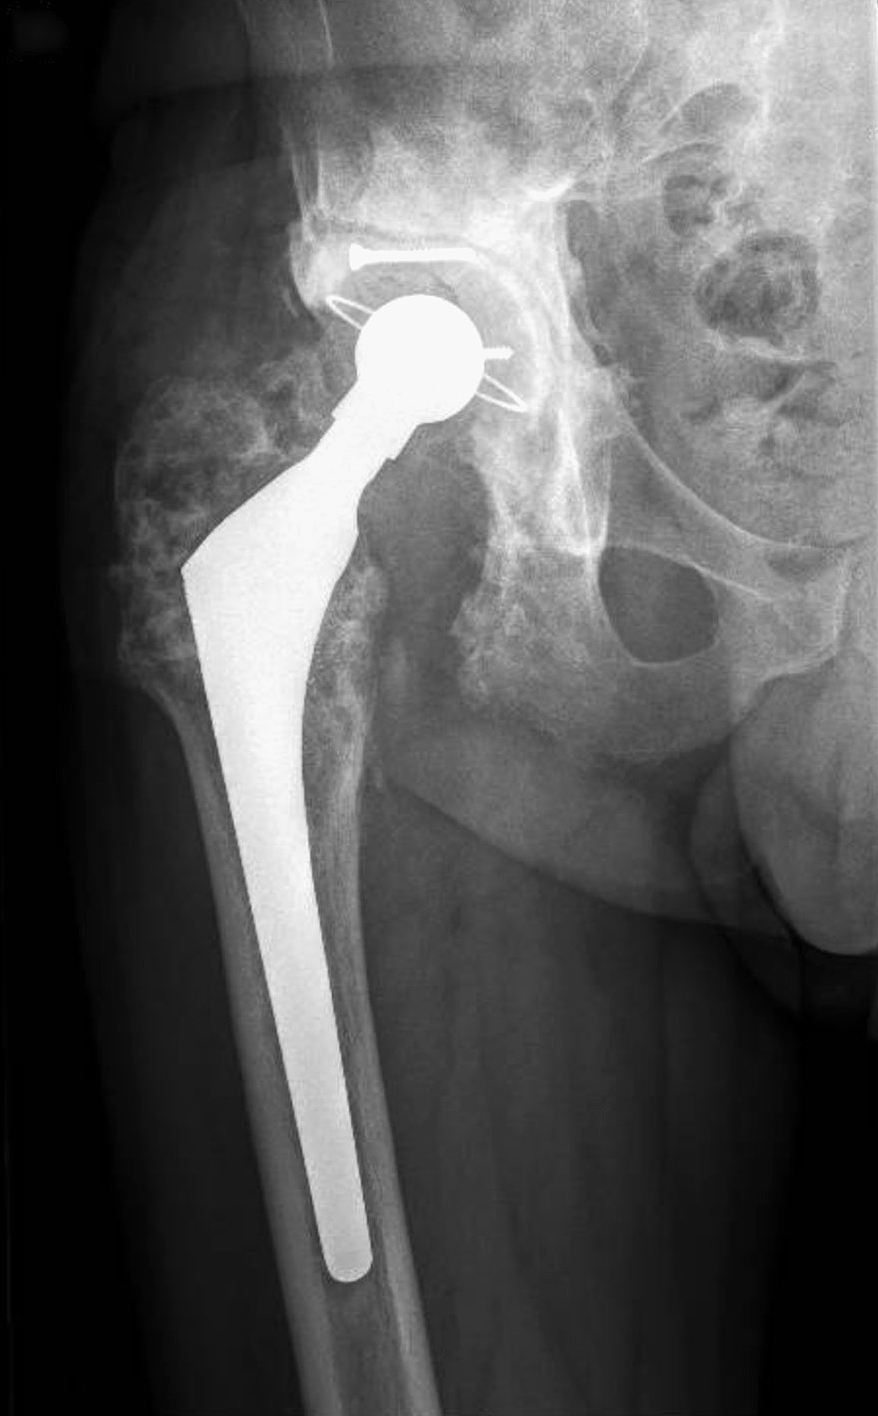

Preoperative X-ray demonstrating severe acetabular bone loss and loosening in a multiply revised right hip.

A 64-year-old male patient with arterial hypertension and no known drug allergies was referred with chronic PJI of the right hip

due to multidrug-resistant Pseudomonas aeruginosa.

His surgical history was complex. Thirty years earlier, he had sustained an acetabular fracture in a road traffic accident that had

been treated with osteosynthesis. This was followed by total hip arthroplasty for post-traumatic osteoarthritis and an early acetabular revision two years later. Subsequently, he developed a PJI that had already been treated with a two-stage exchange. Despite repeated debridements, the infection persisted.

At presentation, clinical examination revealed multiple lateral and posterolateral scars, a proximal fistula with seropurulent discharge, and severely restricted range of motion limited to 0–45° of flexion with absent rotations.

Plain radiographs demonstrated a loose acetabular component, severe acetabular bone loss, and heterotopic ossification.